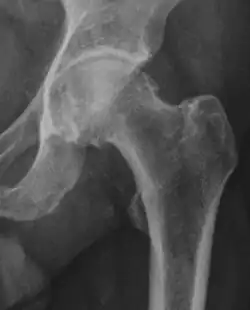

| Femoral head-neck offset | ![]() |

Offset of the femoral head with regard to most prominent aspect of the femora neck | >10 mm |

| Offset percentage | Femoral head-neck offset related to femoral head diameter | >0.18

| |